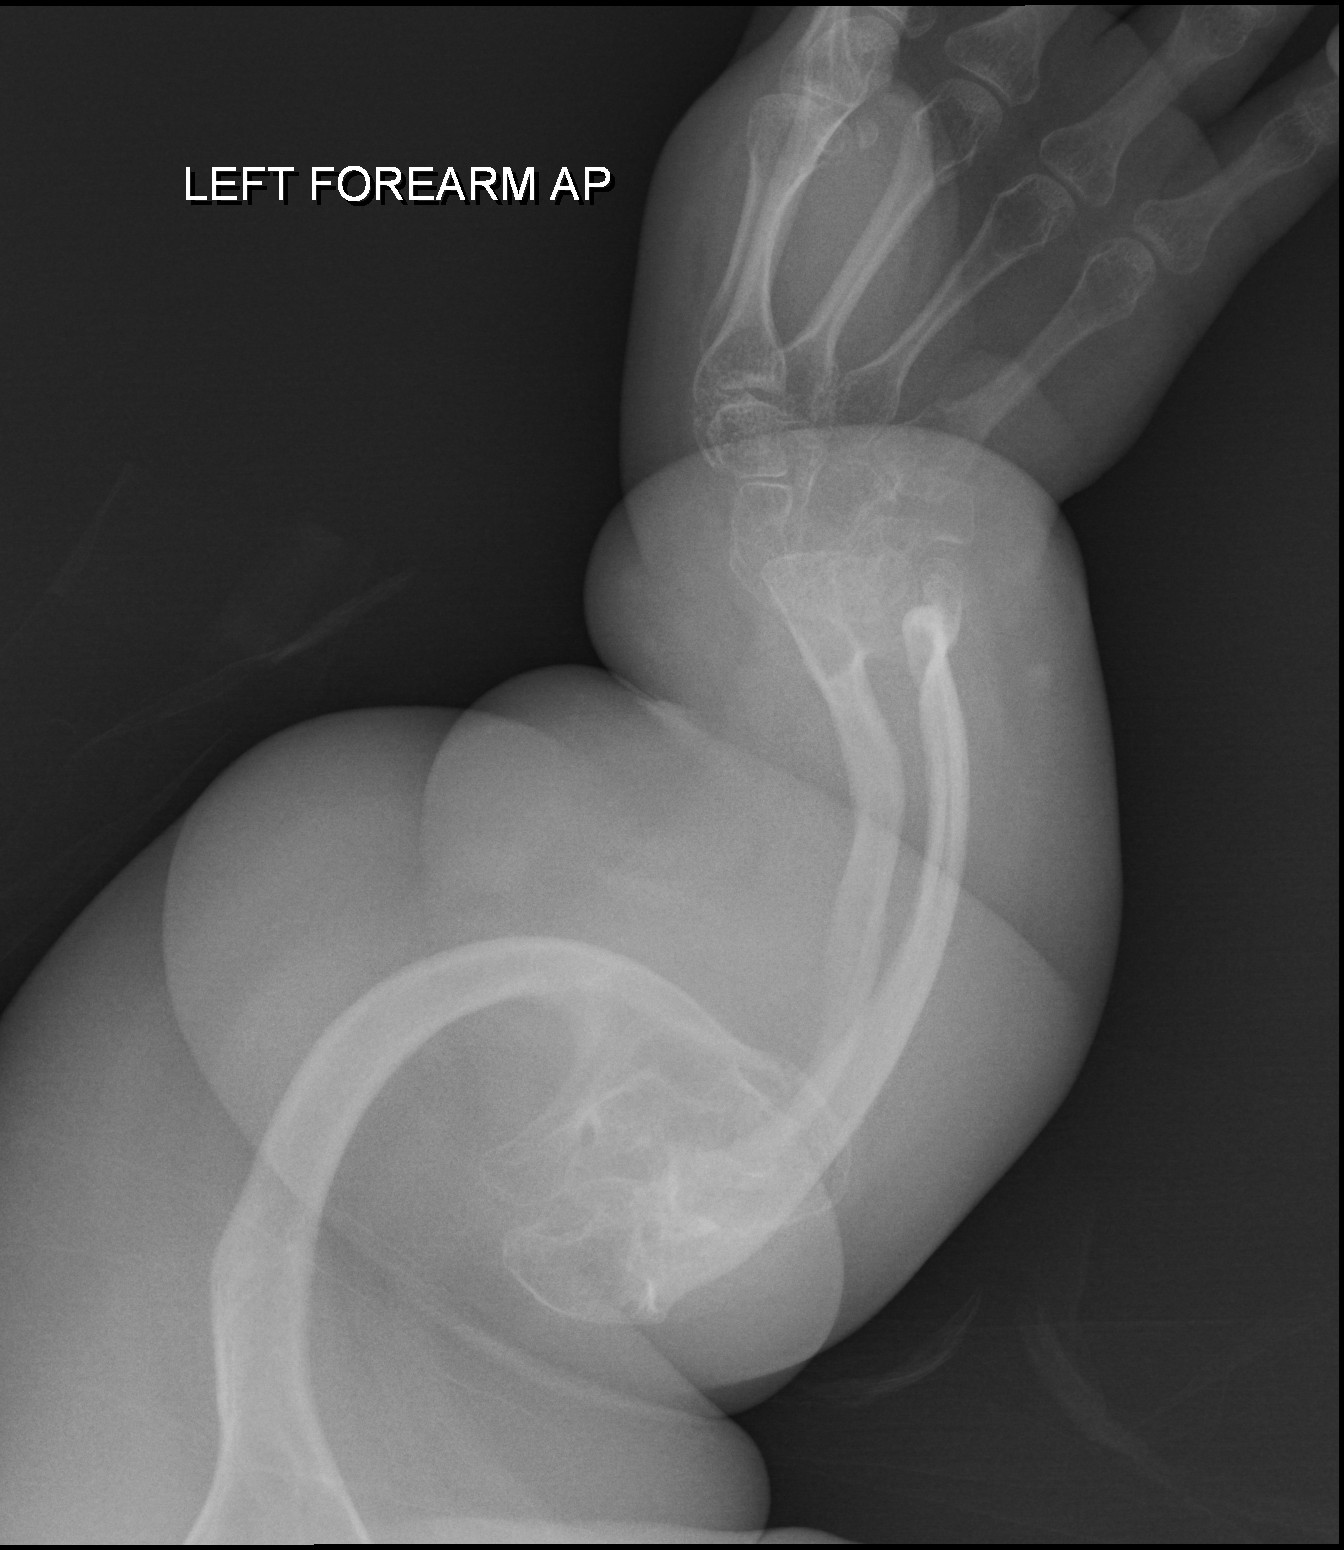

Osteogenesis Imperfekta

Osteogenesis imperfekta (OI) adalah suatu kelainan tulang bawaan (genetik) yang sudah ada saat lahir